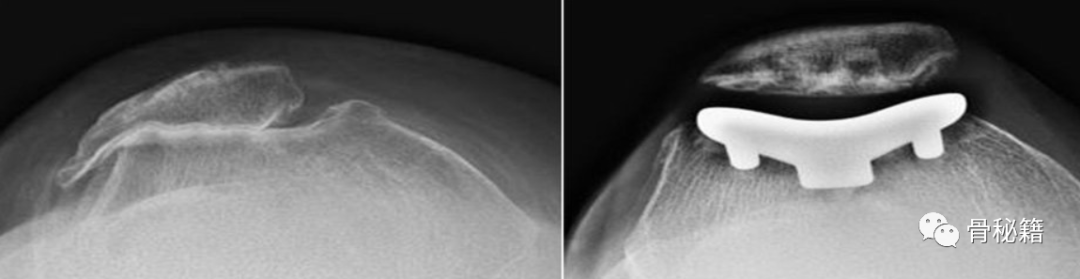

PF 骨关节炎的 Iwano 分类。A I期:关节间隙至少3mm的轻度骨关节炎;B ) II 期:中度骨关节炎,关节间隙 < 3 mm 但无骨接触;C)III期:严重的骨关节炎,骨接触小于关节面的四分之一;D ) IV 期:非常严重的骨关节炎,关节面完全相互接触,通常伴有大的外侧髌骨骨赘,以及外侧髌骨小面的骨质流失

第一个 PFA 于 1955 年由 MacKeever 提出。尽管最初取得了令人鼓舞的结果,但由于滑车槽过度磨损,它很快就被放弃了。PFA 在 1970 年代见证了重生,当时引入了第一代 Richards 假肢(Smith & Nephew),随后在 1990 年代后期随着第二代 PFA 的引入而得到发展。